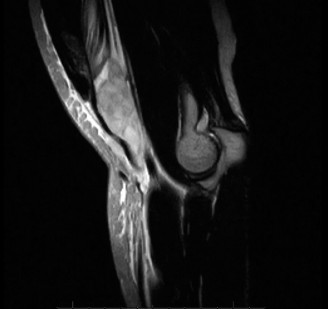

On examination, he has tenderness to palpation over his olecranon and pain with terminal elbow extension. He has no evidence of varus or valgus instability. No pain with resisted wrist flexion. His images are shown (Figs. 2–108 to 2–110).

Figure 2–109

The correct answer is (A). This syndrome occurs most commonly in competitive pitchers, with pain that is worse in the deceleration phase and at terminal extension. The resulting chronic stress results in chondrolysis, osteophyte formation, and attenuation of the MCL. Medial epicondylitis is also common in pitchers, but the pathology is limited to the flexor pronator mass. Pain is over the medial epicondyle and is worse with wrist and forearm flexion. OCD lesions are most common in the capitellum, often present with mechanical symptoms. Olecranon stress fractures result from repetitive abutment into the olecranon fossa. This is a plausible answer, however, the MRI findings are not consistent. MCL rupture is typically acute and is not seen on the MRI shown.